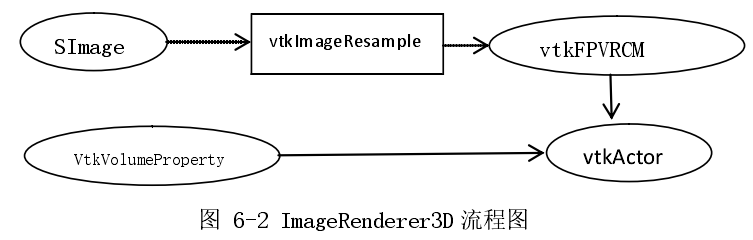

ImageRenderer3D 的主要功能是通过将三维医学图像序列数据进行体绘制并且显示在三维视图上。体绘制采用的是 VTK 中的体绘制类:vtkFixedPointVolumeRayCastMapper 类(流程图中简化称为 vtkFPVRCM)。如图类名这个类就是通过光线投射算法来实现体数据。其配置流程如下图(6-2)所示

光线投射算法已在上文中详细介绍过了,图中 vtkImageResample 用途是对图像进行重采样,渲染流程中除了要对图像序列进行处理外需要创建一个 VtkVolumeProperty 实例,然后在设置好各个属性(颜色透明度属性,rgb 颜色映射等),最后将渲染器和实例传递给最后的成品vtkVolume 实例展示到视图上。